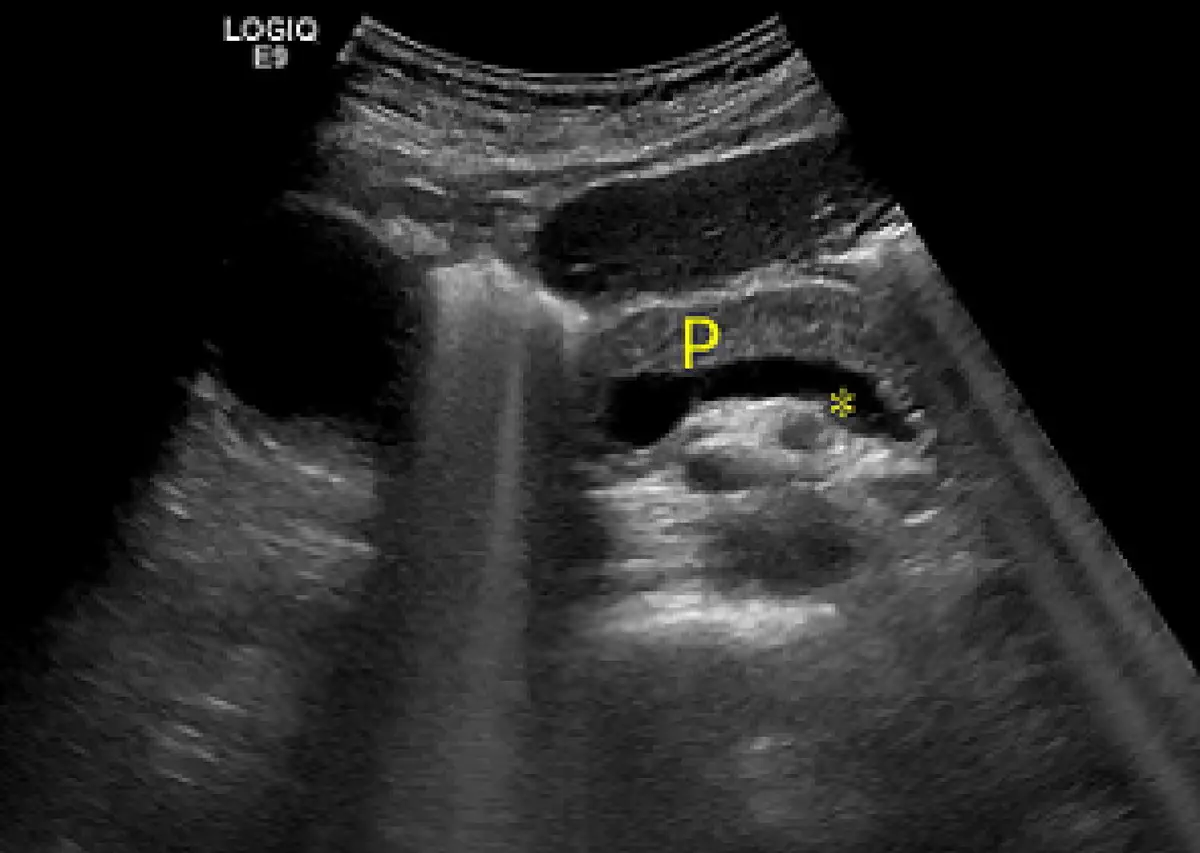

附圖腹部超音波 P為胰臟,星號所指為何?

本影像為 GE LOGIQ E9 超音波機器所攝之上腹部橫切面超音波影像。

影像中央偏上方以黃色字母「P」標示的區塊為胰臟(pancreas),呈均勻中等回音之實質腺體。

在胰臟「P」標示的正後方(下方),可見一條走行於胰臟體部後緣的大型無回音(anechoic)管狀構造,由黃色星號「*」指示。此管狀構造呈現典型血管特徵:

- 管壁平滑、清晰

- 管腔內部完全無回音(呈黑色)

- 沿胰臟體部後緣橫向延伸

這正是脾靜脈的典型超音波表現:脾靜脈走行於胰臟體部與尾部的後緣,在橫切面上呈現長條形無回音管狀構造,是超音波辨識胰臟最重要的血管地標。

(A) 脾靜脈 ✅ 正確 脾靜脈(splenic vein)走行於胰臟體部後緣,在超音波橫切面上呈現緊貼胰臟後表面的管狀無回音構造,是辨識胰臟體部最重要且最可靠的血管標誌。星號所指之位置(胰臟後緣)、走行方向(橫向)、及管腔特徵(無回音)完全符合脾靜脈。